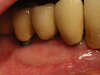

CAS N°5 : poche Parodontale profonde